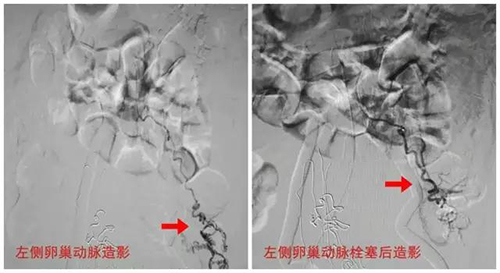

接到急会诊通知后,我院介入医学科治疗团队在第一时间赶到产科,对产妇的情况进行认真仔细的研究后,迅速做出了“立刻完善术前准备,第一时间行介入治疗”的决定。我院介入手术医生在产科医生的积极配合下,迅速将病人转送至介入手术室,常规铺巾、局部麻醉后,熟练地完成腹主动脉、两侧髂内动脉、髂外动脉及子宫动脉造影,可见子宫明显增大,并可见5条子宫供血动脉破裂出血,明确出血动脉后用适量明胶海绵颗粒予以栓堵,栓堵过程中,患者出血量逐渐减少,血压逐步回升。术后患者生命体征平稳,血压130/89mmHg,阴道活动性出血停止,患者脱离生命危险。

经股动脉穿刺,采用直径只有1毫米的导管,在影像设备的引导下,达到子宫供血动脉,造影明确出血的部位后,沿导管注入明胶海绵颗粒对出血动脉进行栓堵,栓堵所用的明胶海绵为中效栓塞剂,破裂血管愈合后,4-6周时间明胶海绵会溶解,血管会再通。栓堵完成后再次复查造影,无出血后拔出导管。